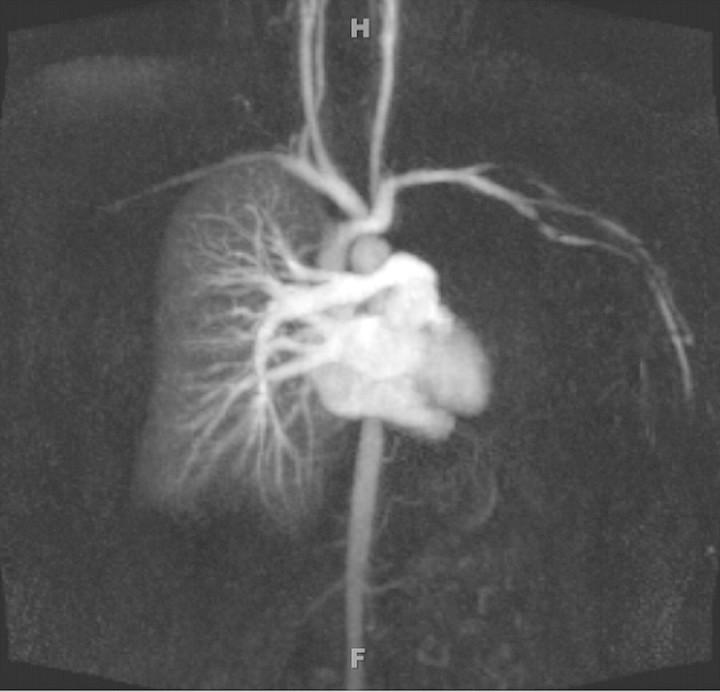

Falling through the cracks of vasculitis classification-a report of three patients.

NDT Plus. 2011 Oct;4(5):327-30. doi: 10.1093/ndtplus/sfr054. Epub 2011 Apr 14.